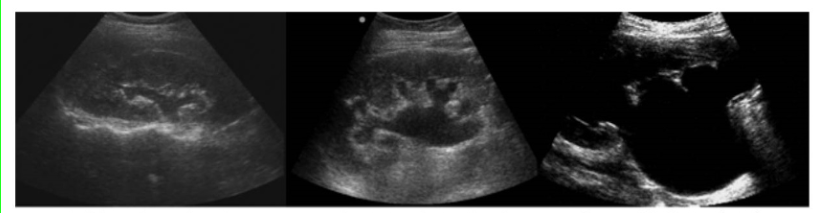

Horseshoe Kidney

Most common fusion anomaly. Lower poles of the kidneys are joined across the midline by a band of soft tissue. +Men. Generally unimpaired – but if obstruction present, surgery possible

horseshoe kidney image

Crossed Ectopia

One kidney lies across the midline and is fused to the other kidney. Second most common fusion anomaly.

crossed ectopia image